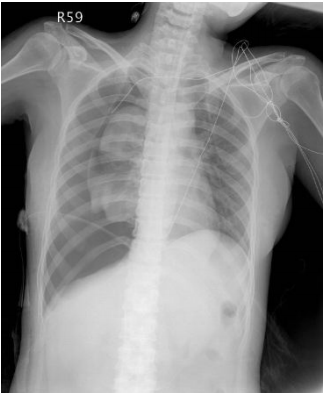

5 一位 15 歲女孩因呼吸急迫就診,過去病史不明,緊急胸部 X 光如附圖。圖中顯示何種必須緊急處理 的問題?

(A) Pneumonia (B) Pneumothorax (C) Internal bleeding (D) Fracture